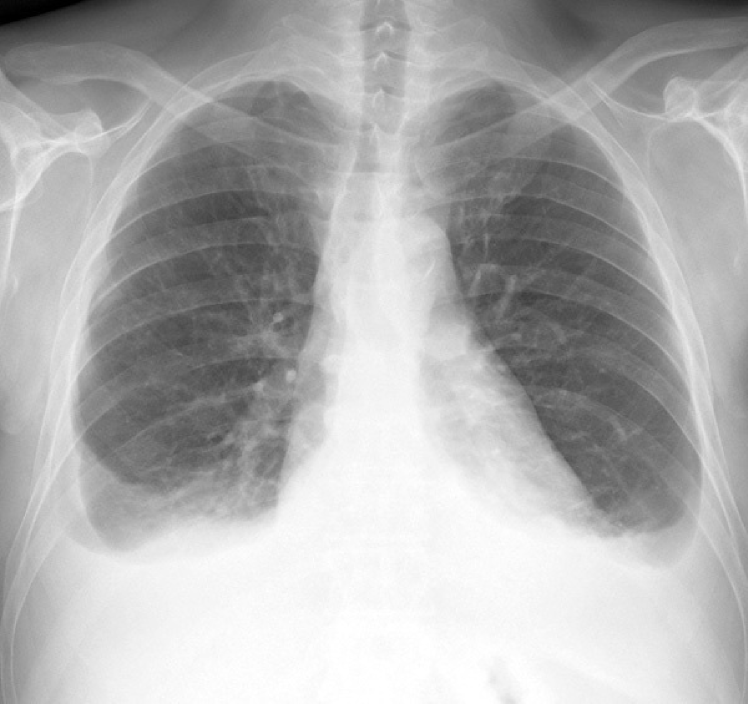

Figure 2: Common chest x-ray projections.

(a) P-A

Refer to caption

(b) Decubit

Figure 4: Pleural effusion in different projections: A bipedestation projection (a) shows the meniscus sign in which the fluid accumulates in the subpulmonary region, ascends through the thoracic wall and through the paramedian zone. In decubit projection (b) there is no meniscus sign. As the liquid goes to the most declining area there is a diffuse increase in hemithorax density and a loss of the net limit of the diaphragm with occupation of the pulmonary vertex by apical cap, costo-phrenic angle blunting and a thickening of the smaller fissure.

The projection information is highly relevant for diagnosis. For example, AP views, which are commonly used in pediatric patients, show an enlarged heart silhouette (Fig. 2(j)) that should not be interpreted as cardiomegaly, but merely the expected large-depth ratio of reversed organ observation (Fig. 3). Another illustrative example is the distinct pattern that pleural effusions have in the standing position (Fig. 4(a)), in which a typical meniscus sign is commonly found as opposed to decubit projections (Fig. 4(b)). Given that the number of different projections is unbalanced (for instance, PA followed by lateral projections typically comprise the majority of chest x-rays), there is the risk that none of the other projections will have sufficient instances with which to train models capable of discriminating pathological from non-pathological patterns in the context of the projection.